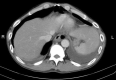

Background: Spontaneous esophageal perforation is a challenging surgical emergency with significant morbidity and mortality, and timely primary repair carries good outcomes. However, direct repair for a delayed spontaneous esophageal perforation is not always feasible and is associated with high mortality. Esophageal stenting can provide therapeutic benefits in the management of esophageal perforations. In this study, we review our experience with placing esophageal stents in combination with minimally-invasive surgical drainage to treat delayed spontaneous esophageal perforations.

Methods: We retrospectively analyzed patients with delayed spontaneous esophageal perforations between September 2018 and March 2021. All patients were treated using a hybrid approach, including esophageal stenting across the gastroesophageal junction (GEJ) to reduce continued contamination, gastric decompression with extraluminal sutures to prevent stent migration, early enteral nutrition, and aggressive minimally-invasive thoracoscopic debridement and drainage of infected material.

Results: There were 5 patients with delayed spontaneous esophageal perforation treated with this hybrid approach. The mean duration between symptoms and diagnosis was 5 days, and the interval between symptoms and esophageal stent insertion was 7 days. The median time to oral nutrition and to esophageal stent removal was 43 and 66 days. There was no stent migration or hospital mortality. Three patients (60%) had postoperative complications. All patients were successfully resumed on oral nutrition with esophageal preservation.

Conclusions: A hybrid approach combining endoscopic esophageal stent placement with extraluminal sutures to prevent stent migration, thoracoscopic decortication with chest tube drainage, gastric decompression, and jejunostomy tube placement for early nutrition was feasible and effective in the treatment of delayed spontaneous esophageal perforations. This technique offers a less invasive treatment approach for a challenging clinical problem which has traditionally carried a high rate of morbidity and mortality.